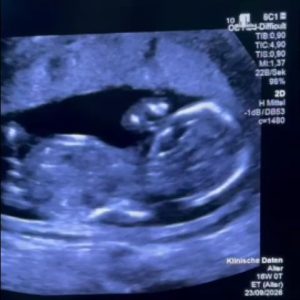

Povestea, scoasă la lumină de Monica Althamer (fost secretar de stat și director de programe la Fundația Metropolis), începe la 12 săptămâni de sarcină. Diagnosticul: megavezică. O malformație care, deși sună intimidant, este tratabilă intrauterin. Procedura este clară: montarea unui shunt vezico-amniotic care să preia presiunea de pe rinichii fătului și să permită dezvoltarea plămânilor.

Experții europeni sunt categorici: fereastra de intervenție este între săptămânile 11 și 16. Dincolo de acest prag, distrugerile pot fi ireversibile.

672182301 26367271899632542 9155863517583703225 n - Starea de sanatateIntervenția a fost realizată cu succes de profesorul Thomas Kohl a doua zi după Paștele Catolic. Specialistul german s-a declarat șocat de consilierea „extrem de slabă” primită de pacientă în România, menționând că stentul a fost montat în ultimul moment, când vezica fătului ajunsese deja de dimensiunea capului acestuia.